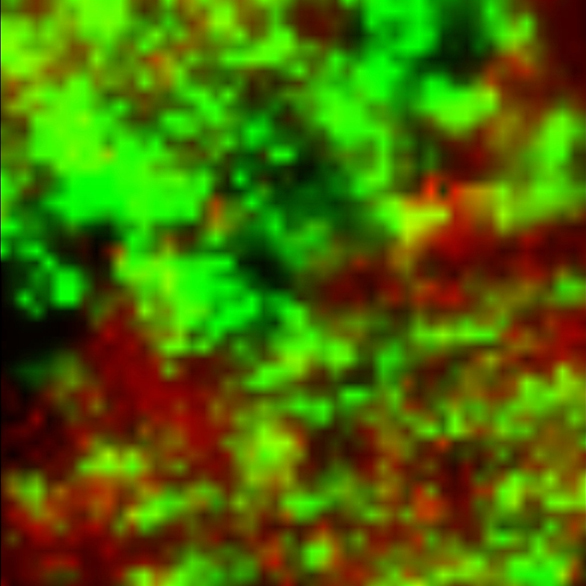

Характеристичные спектры аспирина и парацетамола использованы для построения карты распределения химических компонентов в таблетке (Рис. 2). Возможно видеть гомогенное распределение активных компонентов в исследованной таблетке (Рис. 2).